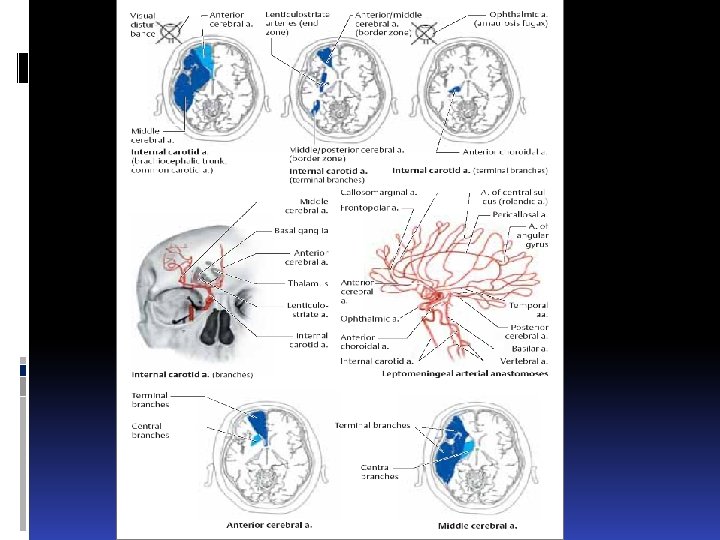

Types of infarct. There are three basic types of brain infarct, distinguished from each other by the caliber of the occluded arteries: Territorial infarcts are mainly produced by occlusions of the main trunks or major branches of cerebral arteries (cerebral macroangiopathy), which may be due to thrombosis, embolism, or other causes. The infarct includes both cortex and subcortical white matter and sometimes the basal ganglia and thalamus (Fig. 6. 12). It is usually possible to infer which vessel has been occluded from the pattern of neurological deficits that are produced.

Types of infarct. There are three basic types of brain infarct, distinguished from each other by the caliber of the occluded arteries: Territorial infarcts are mainly produced by occlusions of the main trunks or major branches of cerebral arteries (cerebral macroangiopathy), which may be due to thrombosis, embolism, or other causes. The infarct includes both cortex and subcortical white matter and sometimes the basal ganglia and thalamus (Fig. 6. 12). It is usually possible to infer which vessel has been occluded from the pattern of neurological deficits that are produced.

В бассейне А. cerebri anterior спастический парез ноги лобная атаксия расстройства чувствительности гемиспазм лица Лобная психика, апраксия

В бассейне А. cerebri anterior спастический парез ноги лобная атаксия расстройства чувствительности гемиспазм лица Лобная психика, апраксия

В бассейне А. cerebri media Астереогнозия Аутотопагнозия Слуховая агнозия Апраксия Агнозия Сенсомоторная афазия

В бассейне А. cerebri media Астереогнозия Аутотопагнозия Слуховая агнозия Апраксия Агнозия Сенсомоторная афазия

В бассейне А. cerebri posterior Зрительная агнозия Алексия Таламический синдром Альтернирую- щий синдром Вебера

В бассейне А. cerebri posterior Зрительная агнозия Алексия Таламический синдром Альтернирую- щий синдром Вебера